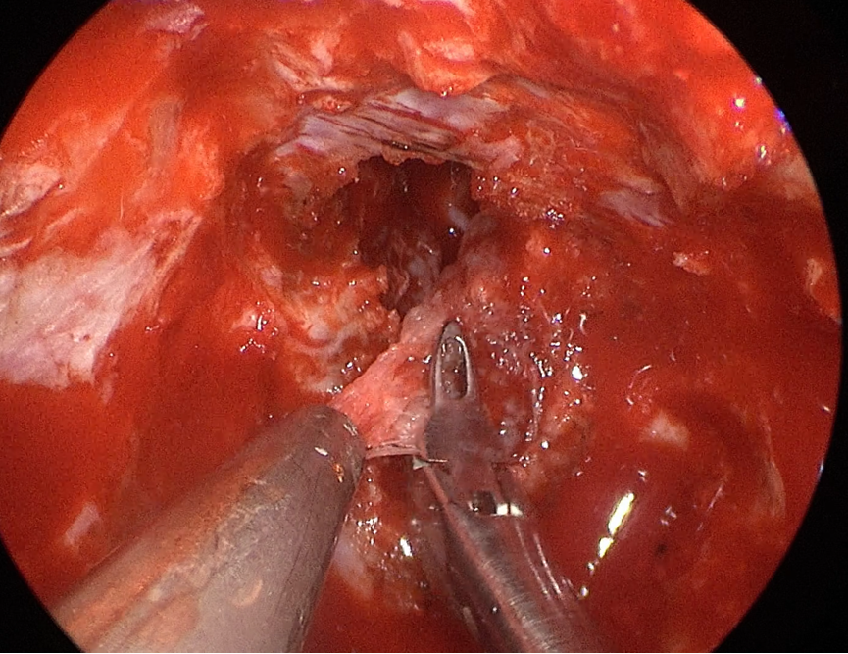

自近蝶窦前壁处向左侧推挤鼻中隔,离断筛骨垂直板,咬除部分近蝶窦处骨性鼻中隔,分离双侧鼻粘膜显露蝶窦前壁,自蝶窦开口上方做沿鼻中隔做粘膜瓣备用,末端到中鼻甲位置,将粘膜瓣压向下鼻道,高速磨钻磨除蝶窦下壁骨质,鞍结节骨质。术中视神经管清晰可见,给予保护,海绵间窦出血给予流体明胶+凝血酶止血;等离子刀一边止血一边切开硬脑膜见白色肿瘤质韧,边界清晰,大脑前动脉分支粘连于肿瘤表面,给予小心分离,以刮圈,咬切钳等小心清除肿瘤组织;内镜下将肿瘤完整切除;取右侧大腿皮下脂肪及阔筋膜备用,以人工硬膜修补和明胶海绵封闭鞍底硬膜,将脂肪放置于切口,并缝合于鞍底硬脑膜上固定铺平,阔筋膜覆盖于脂肪外边,蝶窦内充填明胶海绵止血,鼻粘膜瓣覆盖于蝶窦;碘仿纱条填塞鼻腔;护士清点棉条、器械、纱布无误,撤出鼻镜。